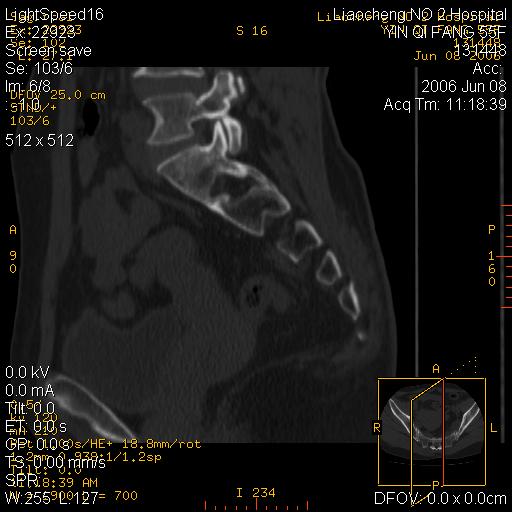

女,55岁,十余年前骶尾骨摔伤,x线平片诊断骶骨裂纹骨折,现在骶尾部又疼痛2月,x线怀疑骶骨左下部骨质破坏。大家看看,是不是先天变异。正常人不是只有4个骶孔吗?怎么此病例有5个?

众口一词啊,图象确实漂亮,羡煞人也!右侧骶髂关节间隙变窄,相对缘增生硬化,髂骨侧增生明显。左侧轻微类似改变,考虑双侧骶髂关节炎。余未见异常。

五个孔也是正常的呀;